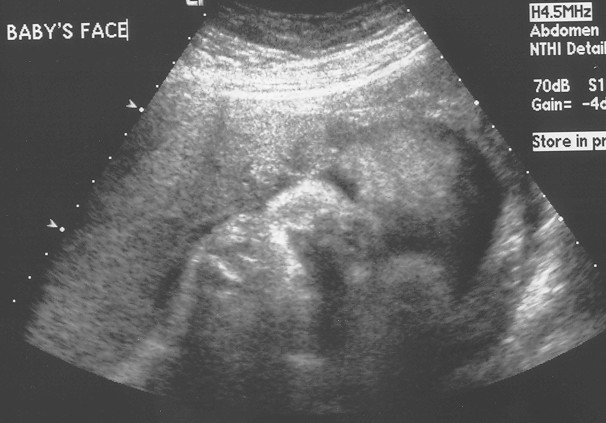

Abigail Preview: 35 weeks